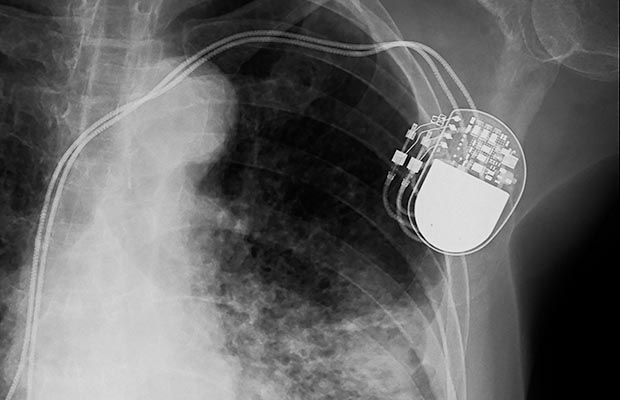

Many people with a pacemaker or ICD (implantable cardioverter defibrillator) have a remote monitor. This is a device plugged in at home, usually next to your bed, that sends information from the device in your chest to your cardiac centre. Home monitoring allows your specialist to see how your device is behaving, check the battery status and monitor any changes in your heart rhythm. This helps to keep you safe and allows your specialist to act early to address any issues that might need medical attention, or a review of your medication.

How does a pacemaker work?